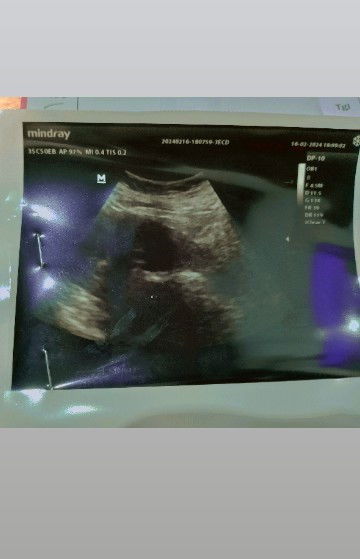

Bunda minta tolong masukannya 🙏🏻saya hamil 14w dan 2 hari yg lalu saya tiba-tiba nyeri perut hebat sebelah kanan. USG ke klinik dokter umum, janin masih didalam kandungan tp denyut jantung melebihi normal jd disarankan untuk segera dirujuk ke RS. Sesampainya di RS Dokter kandungan bilang saya terkena ISK&itu normal gapapa. Jadi saya ga di USG ulang. Selang 2 hari saya diopname, baru hari ini saya nyeri hebat kembali padahal sudah banyak obat saya teguk, pun juga lewat infusnya. Hari ini suami saya minta untuk USG kemudian dokter kandungan berubah diagnosa nya menjadi kemungkinan janin saya berada diluar kandungan. Tapi dokter tidak langsung menindaklanjuti&minta untuk observasi dulu. Memasukan obat melalui anus saya. Pertanyaan saya. Apakah bisa hamil diluar kandungan setelah sudah 14w ini? Yg padahal sebelumnya setiap 2 Minggu sekali selalu USG dinyatakan semuanya baik aja 🥹 barangkali ada yg punya pengalaman yg sama/ pun punya pengalaman hamil diluar kandungan dengan usia kehamilan diatas 8w 🙏🏻#SeriusTanya #bantujawab #bantusharing #ingintahu #Sharing_dong_Bund